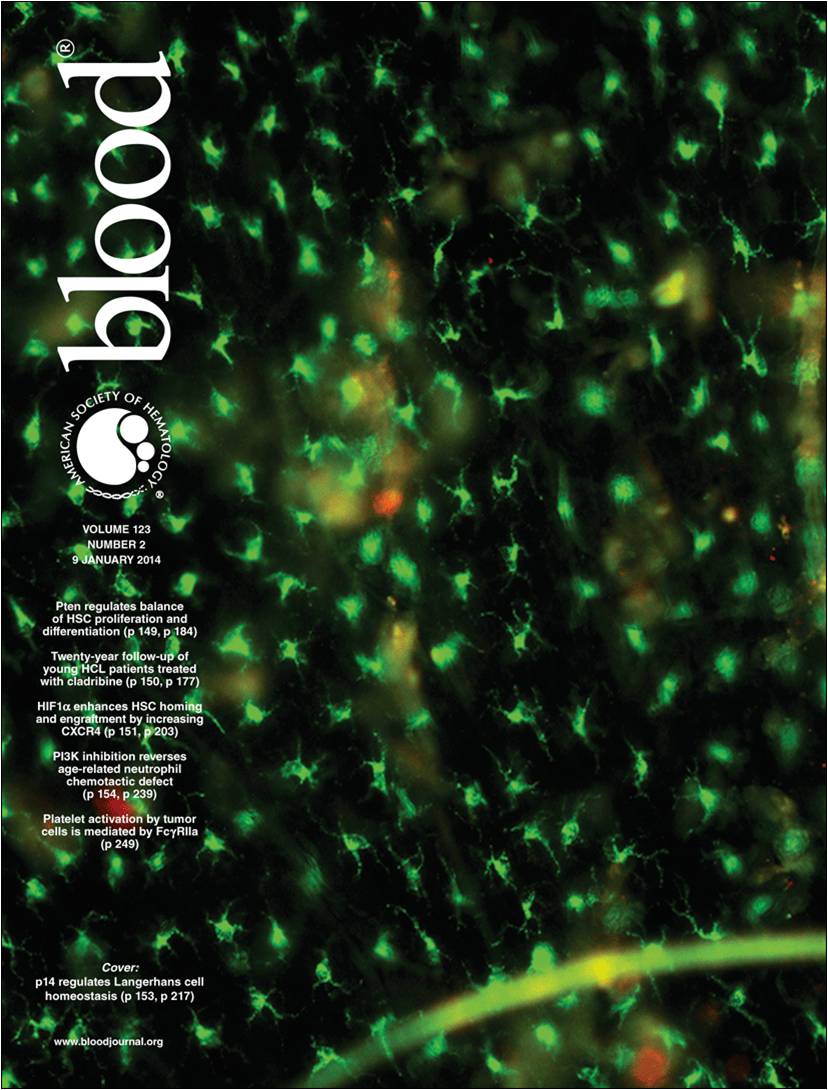

Eine kürzlich im Fachjournal BLOOD publizierte Arbeit zweier Forschungsteams aus der Innsbrucker Hautklinik und dem Biozentrum trägt entscheidend zum besseren Verständnis der Regulation des Lebenszyklus epidermaler Langerhanszellen bei. Die Bedeutung der Ergebnisse wird auch dadurch unterstrichen, dass sie dem Journal einen Kommentar – „Inside Blood“ – wert waren und ein Langerhanszell-Foto von Erstautor Dr. Florian Sparber das Titelblatt des aktuellen Heftes ziert.

Dr. Florian Sparbers Foto ist das aktuelle BLOOD-Titelbild. |